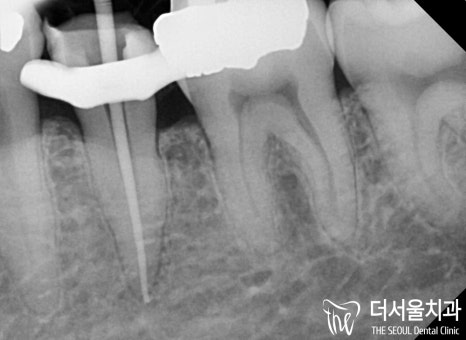

감염이 생긴 곳을 깨끗하게 삭제한 뒤

치과용 충전재를 사용하여

뿌리 끝까지 확실하게 밀폐시켰습니다

이후 병소가 확실하게 잡힌 것을

확인한 뒤에 보철 제작을 돕기로 했는데요.

그전, 코어 작업을 마친 뒤

크라운을 씌울 표면을 미리 다듬어주는

프랩 과정까지 마쳤습니다.